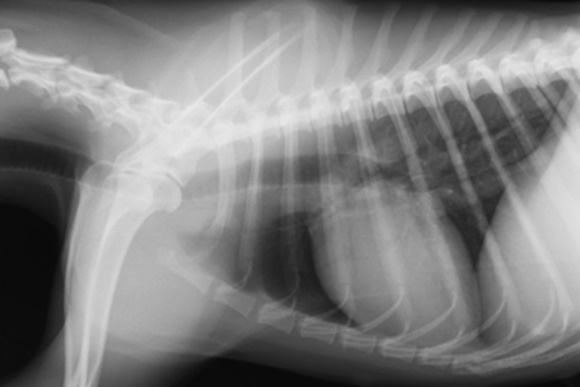

Στην εικόνα φαίνεται η ακτινογραφία θώρακα σε ένα ηλικιωμένο σκύλο που παρουσιάζει αναγωγές. Ο σκύλος δεν έχει άλλα συμπτώματα. Η